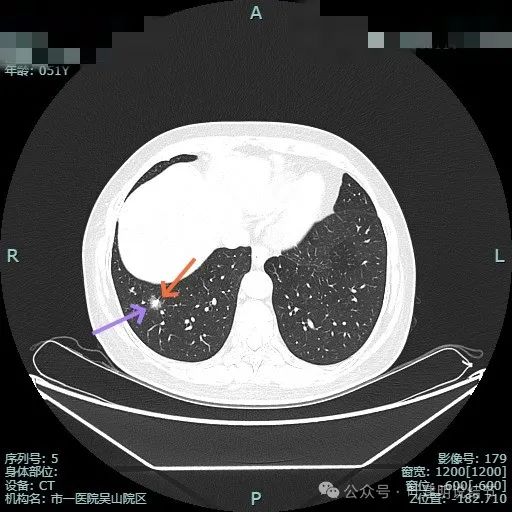

明显的血管进入与异常增粗。

灶内密度杂乱,血管进入与增粗,表面不平。

实性成分明显,但缺乏收缩力;边上是磨玻璃成分,整体轮廓较清;邻近血管走行,但没有形成血管弯征。

边缘毛糙,但瘤肺边界欠清,灶内实性成分缺乏收缩力。